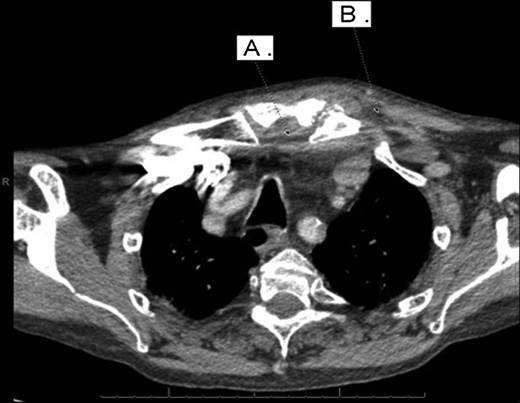

With a working differential of parapharyngeal space infection and possible malignancy, the patient was referred for a computed tomography (CT) scan of the neck and thorax with contrast. The patient was also started empirically on intravenous co-amoxiclav as treatment for neck space collection. CT imaging, performed 24 h after admission, revealed no evidence of malignancy or indeed any paraphayrngeal space collection. Few small lymph nodes were noted on the left side of the neck, but were deemed to be reactive in nature, and left vocal cord palsy was evident (Fig. 1). The key finding was that of a left sternoclavicular joint collection and closely associated superficial anterior chest wall, soft tissue swelling and oedema (Fig. 2). This inflammatory process was also noted deep to the manubrium and sternum and extending somewhat into the mediastinum with evident enlarged mediastinal lymph nodes (Fig. 3). The CT findings were in keeping with SSA with associated superficial and deep tissue inflammation and oedema. With no other cause found, the vocal cord palsy was attributed to the inflammation within the mediastinum, which in turn was caused by superficial burn from hot water bottle use.

Computed tomography. A 67-year-old male with SSA. Findings: left vocal cord palsy indicated by the para-median position of the left vocal cord in comparison with the right. Technique: contrast-enhanced axial CT of the neck and thorax.